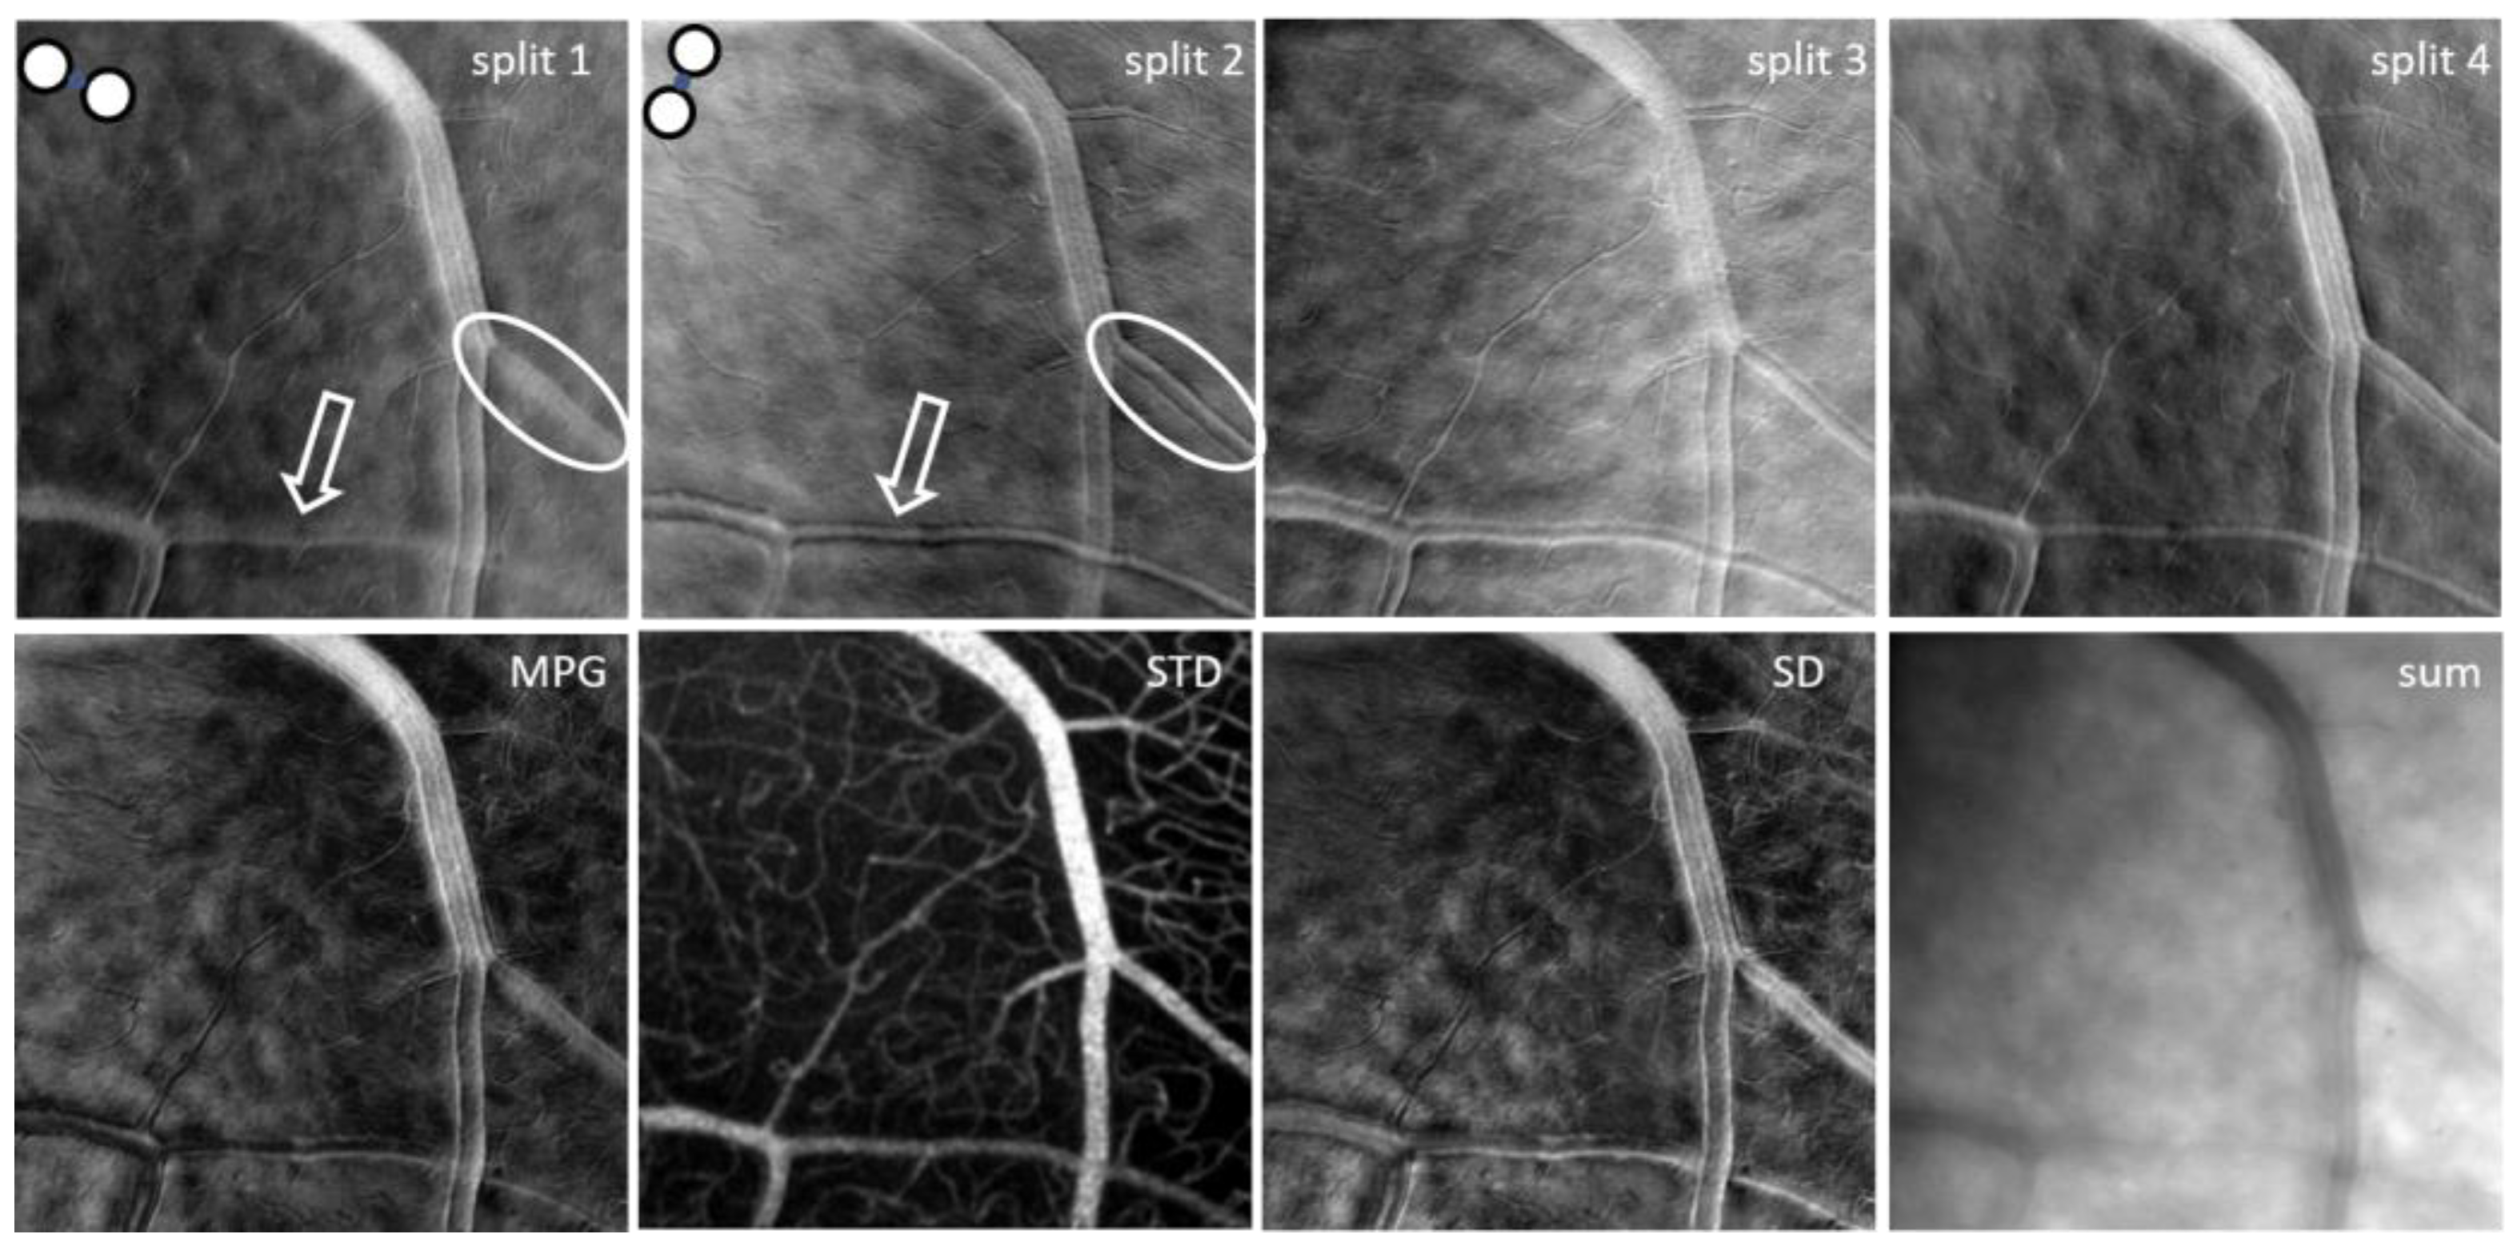

2. Materials and Methods

2.3. Confocal and Non-Confocal Imaging

3. Results